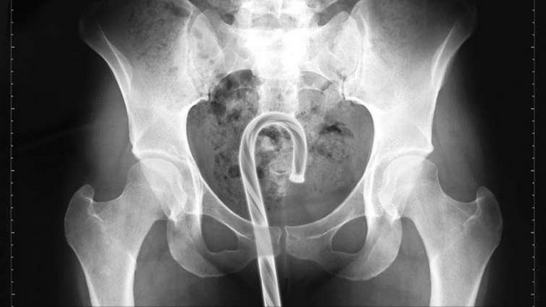

Garfo:

Se fosse pelo menos uma colher, mas o garfo é ruim de retirar porque pode perfurar algum órgão, que situação mais grotesca hein?